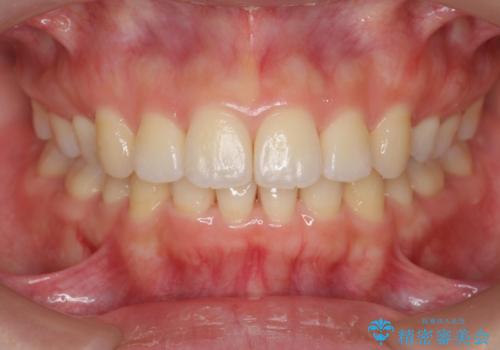

再矯正 昔ワイヤーで治療 前歯の並びを再度きれいに

- 小さいころに小臼歯を抜歯しワイヤー矯正をしたが、すき間が空いてきて、前歯の並びが戻ってしまったとのこと。

インビザラインライトという部分矯正コースで、全体矯正に比べ、比較的安価に治療しました。

前歯の並びが格段にきれいになり、大変喜んでいただけました。